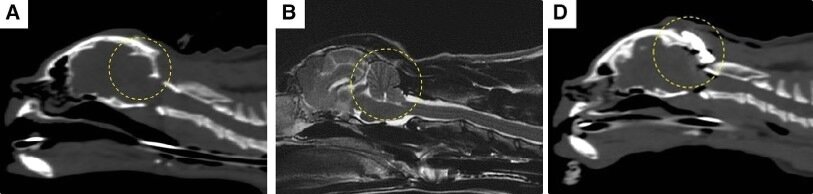

본문 이미지 - 페르시안 고양이에서 시행된 후두공 감압술 및 두개골 성형술의 수술 전후 영상(넬동물의료센터 제공) ⓒ 뉴스1

페르시안 고양이에서 시행된 후두공 감압술 및 두개골 성형술의 수술 전후 영상(넬동물의료센터 제공) ⓒ 뉴스1